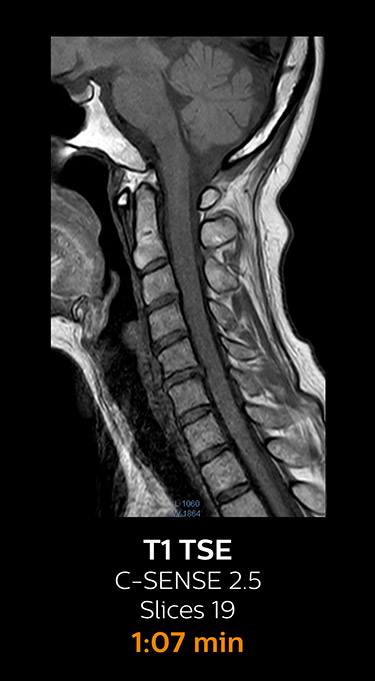

Fast MRI of cervical spine

With Compressed SENSE, the scan time for the routine cervical spine examination at KNC was reduced from 13:11 to 9:52 minutes, which corresponds to 25% reduction.

MRI examination of cervical spine with Compressed SENSE

MRI examination of the cervical spine with Compressed SENSE

Ingenia 3.0T CX

Scan time 9:52 min. (was 13:11 min. without Compressed SENSE)